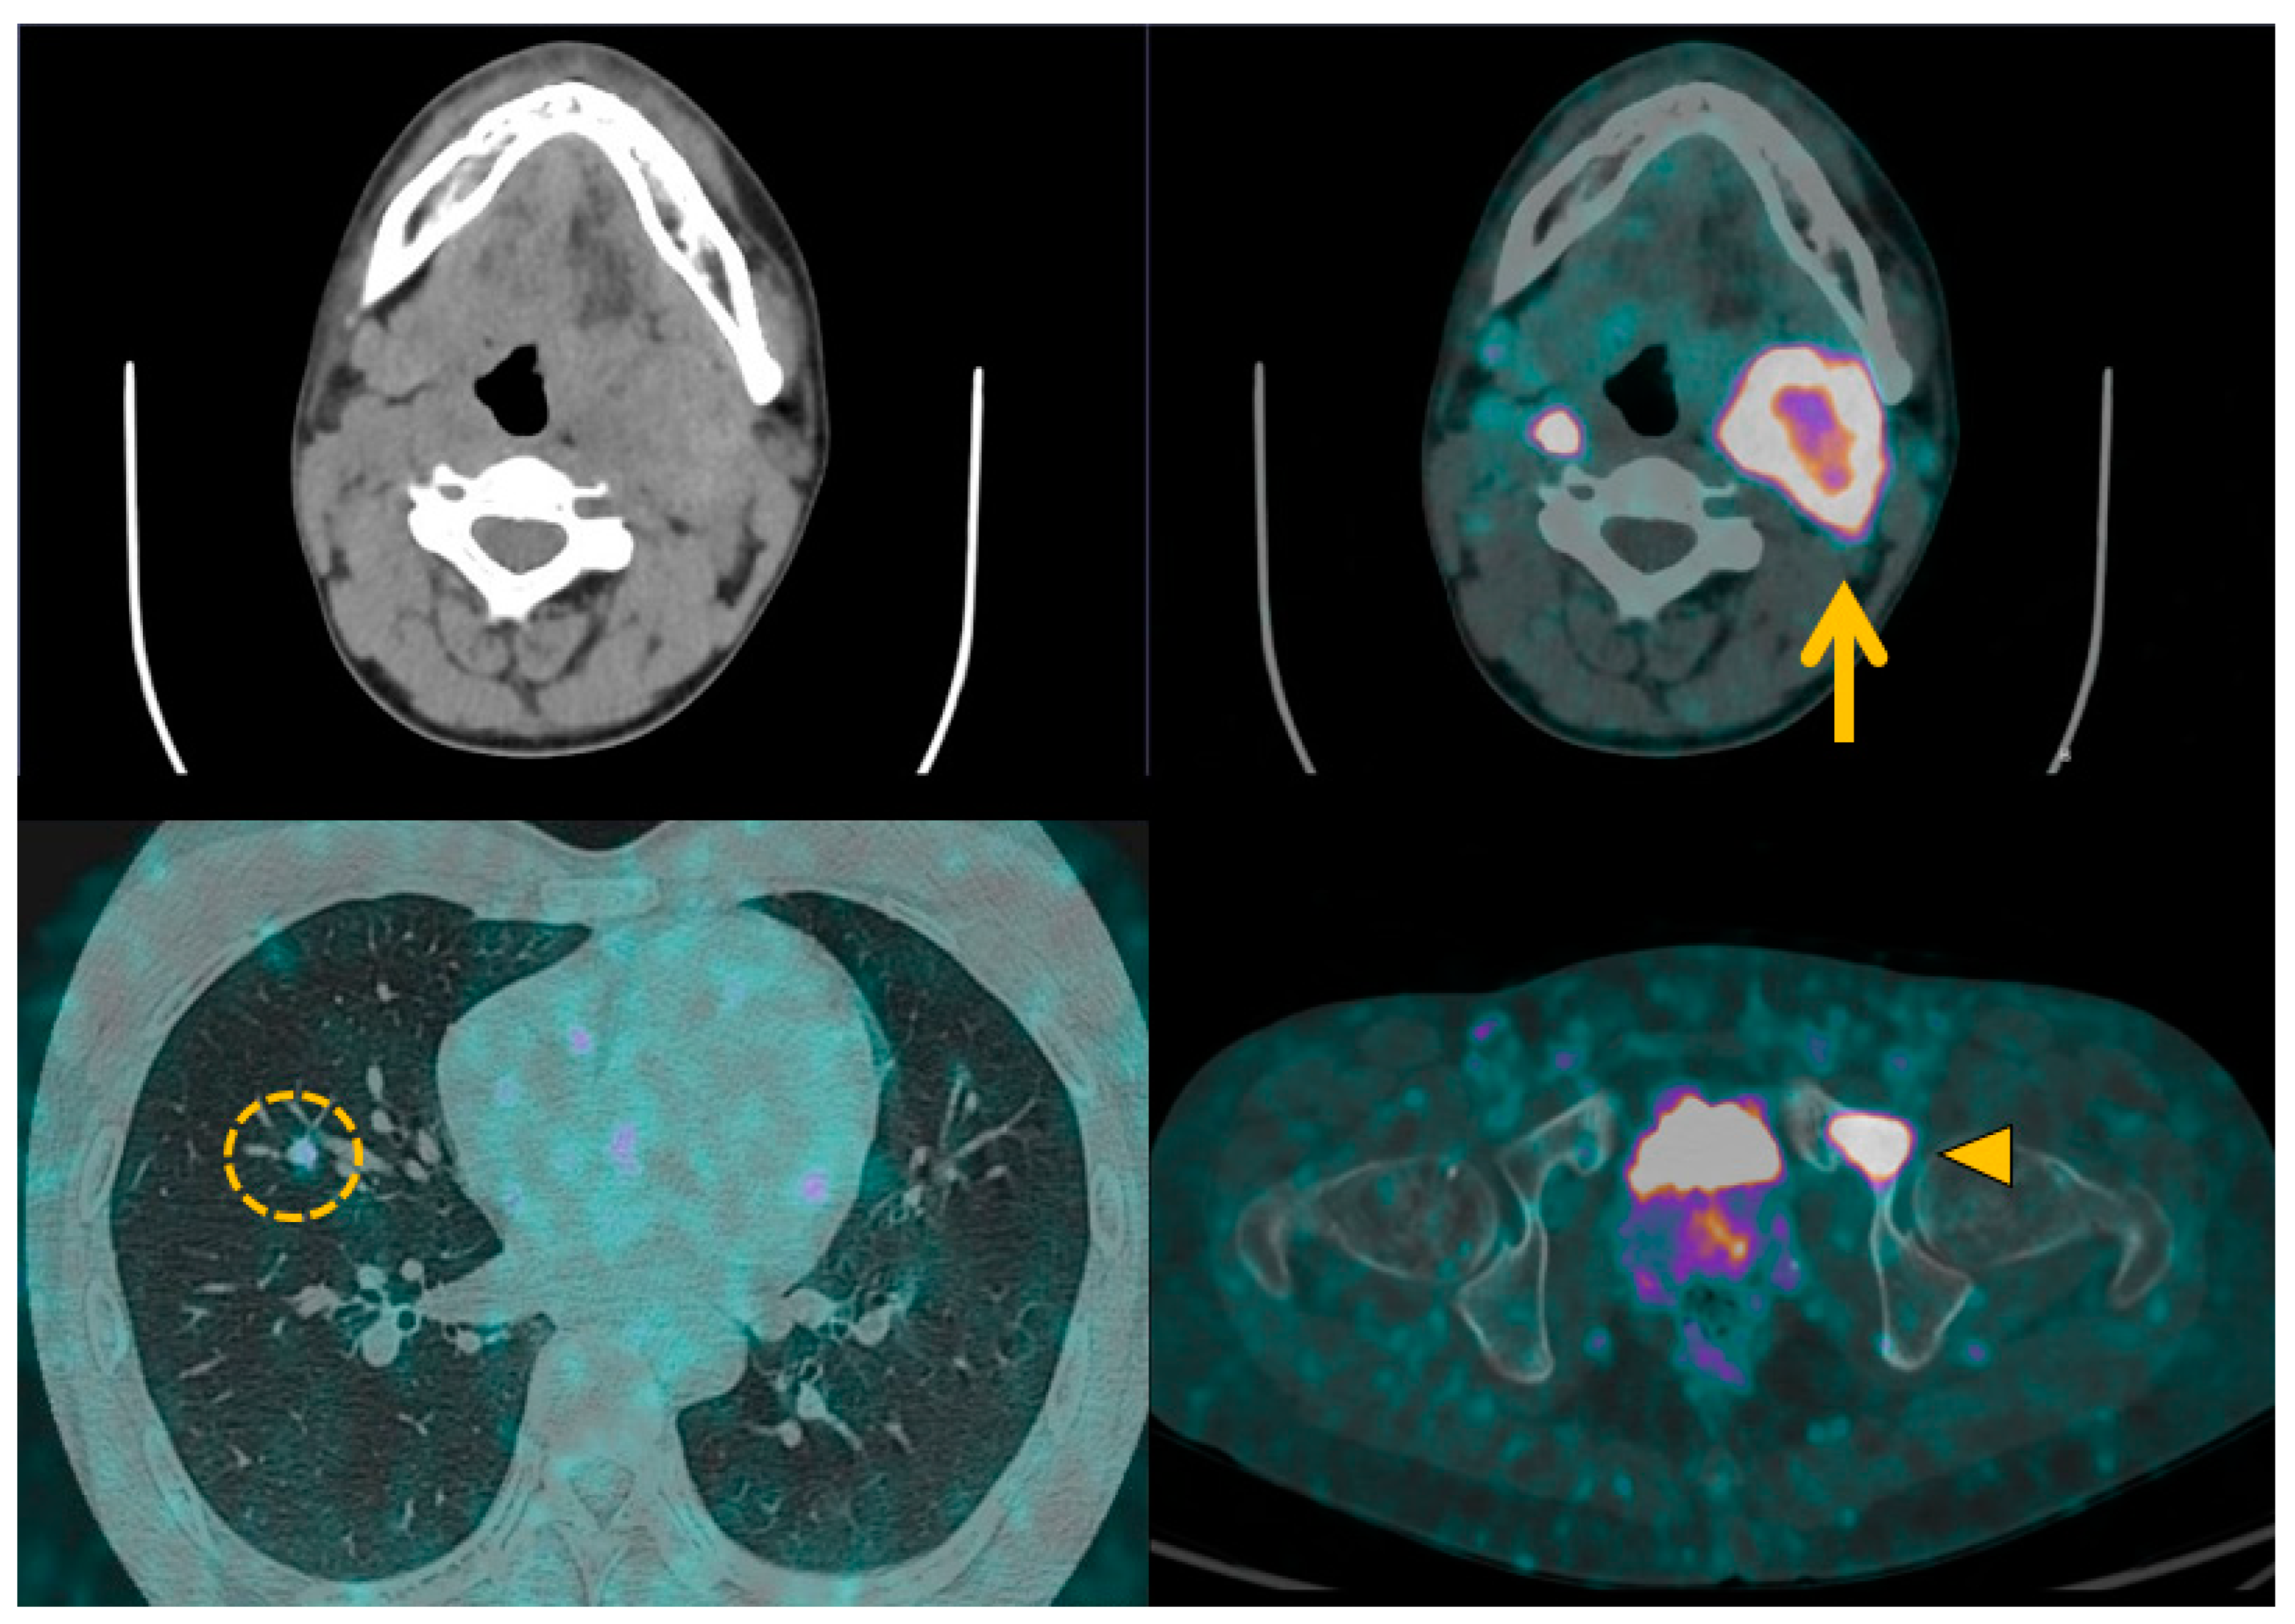

3.5. Head and Neck Parangangliomas: Specific Concerns

3.6. Specific Concern: How to Manage Asymptomatic SDHx Mutation Carriers?

4.3. Positron Emission Tomography with Computed Tomography Using Somatostatin Analogues

4.4. Current Guidelines for Molecular Imaging in Diagnosis and Staging of PPGLs